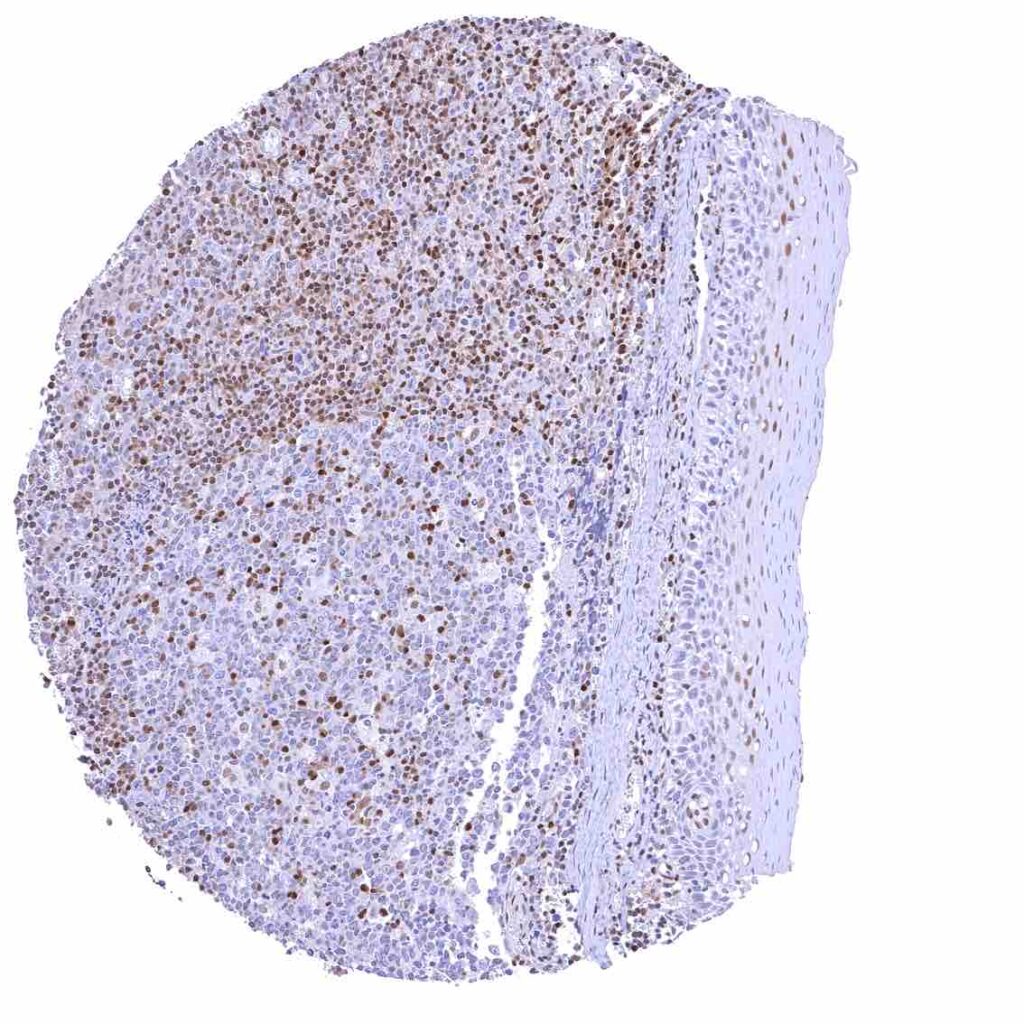

Spleen – Strong nuclear p27 staining of a large fraction of cells.